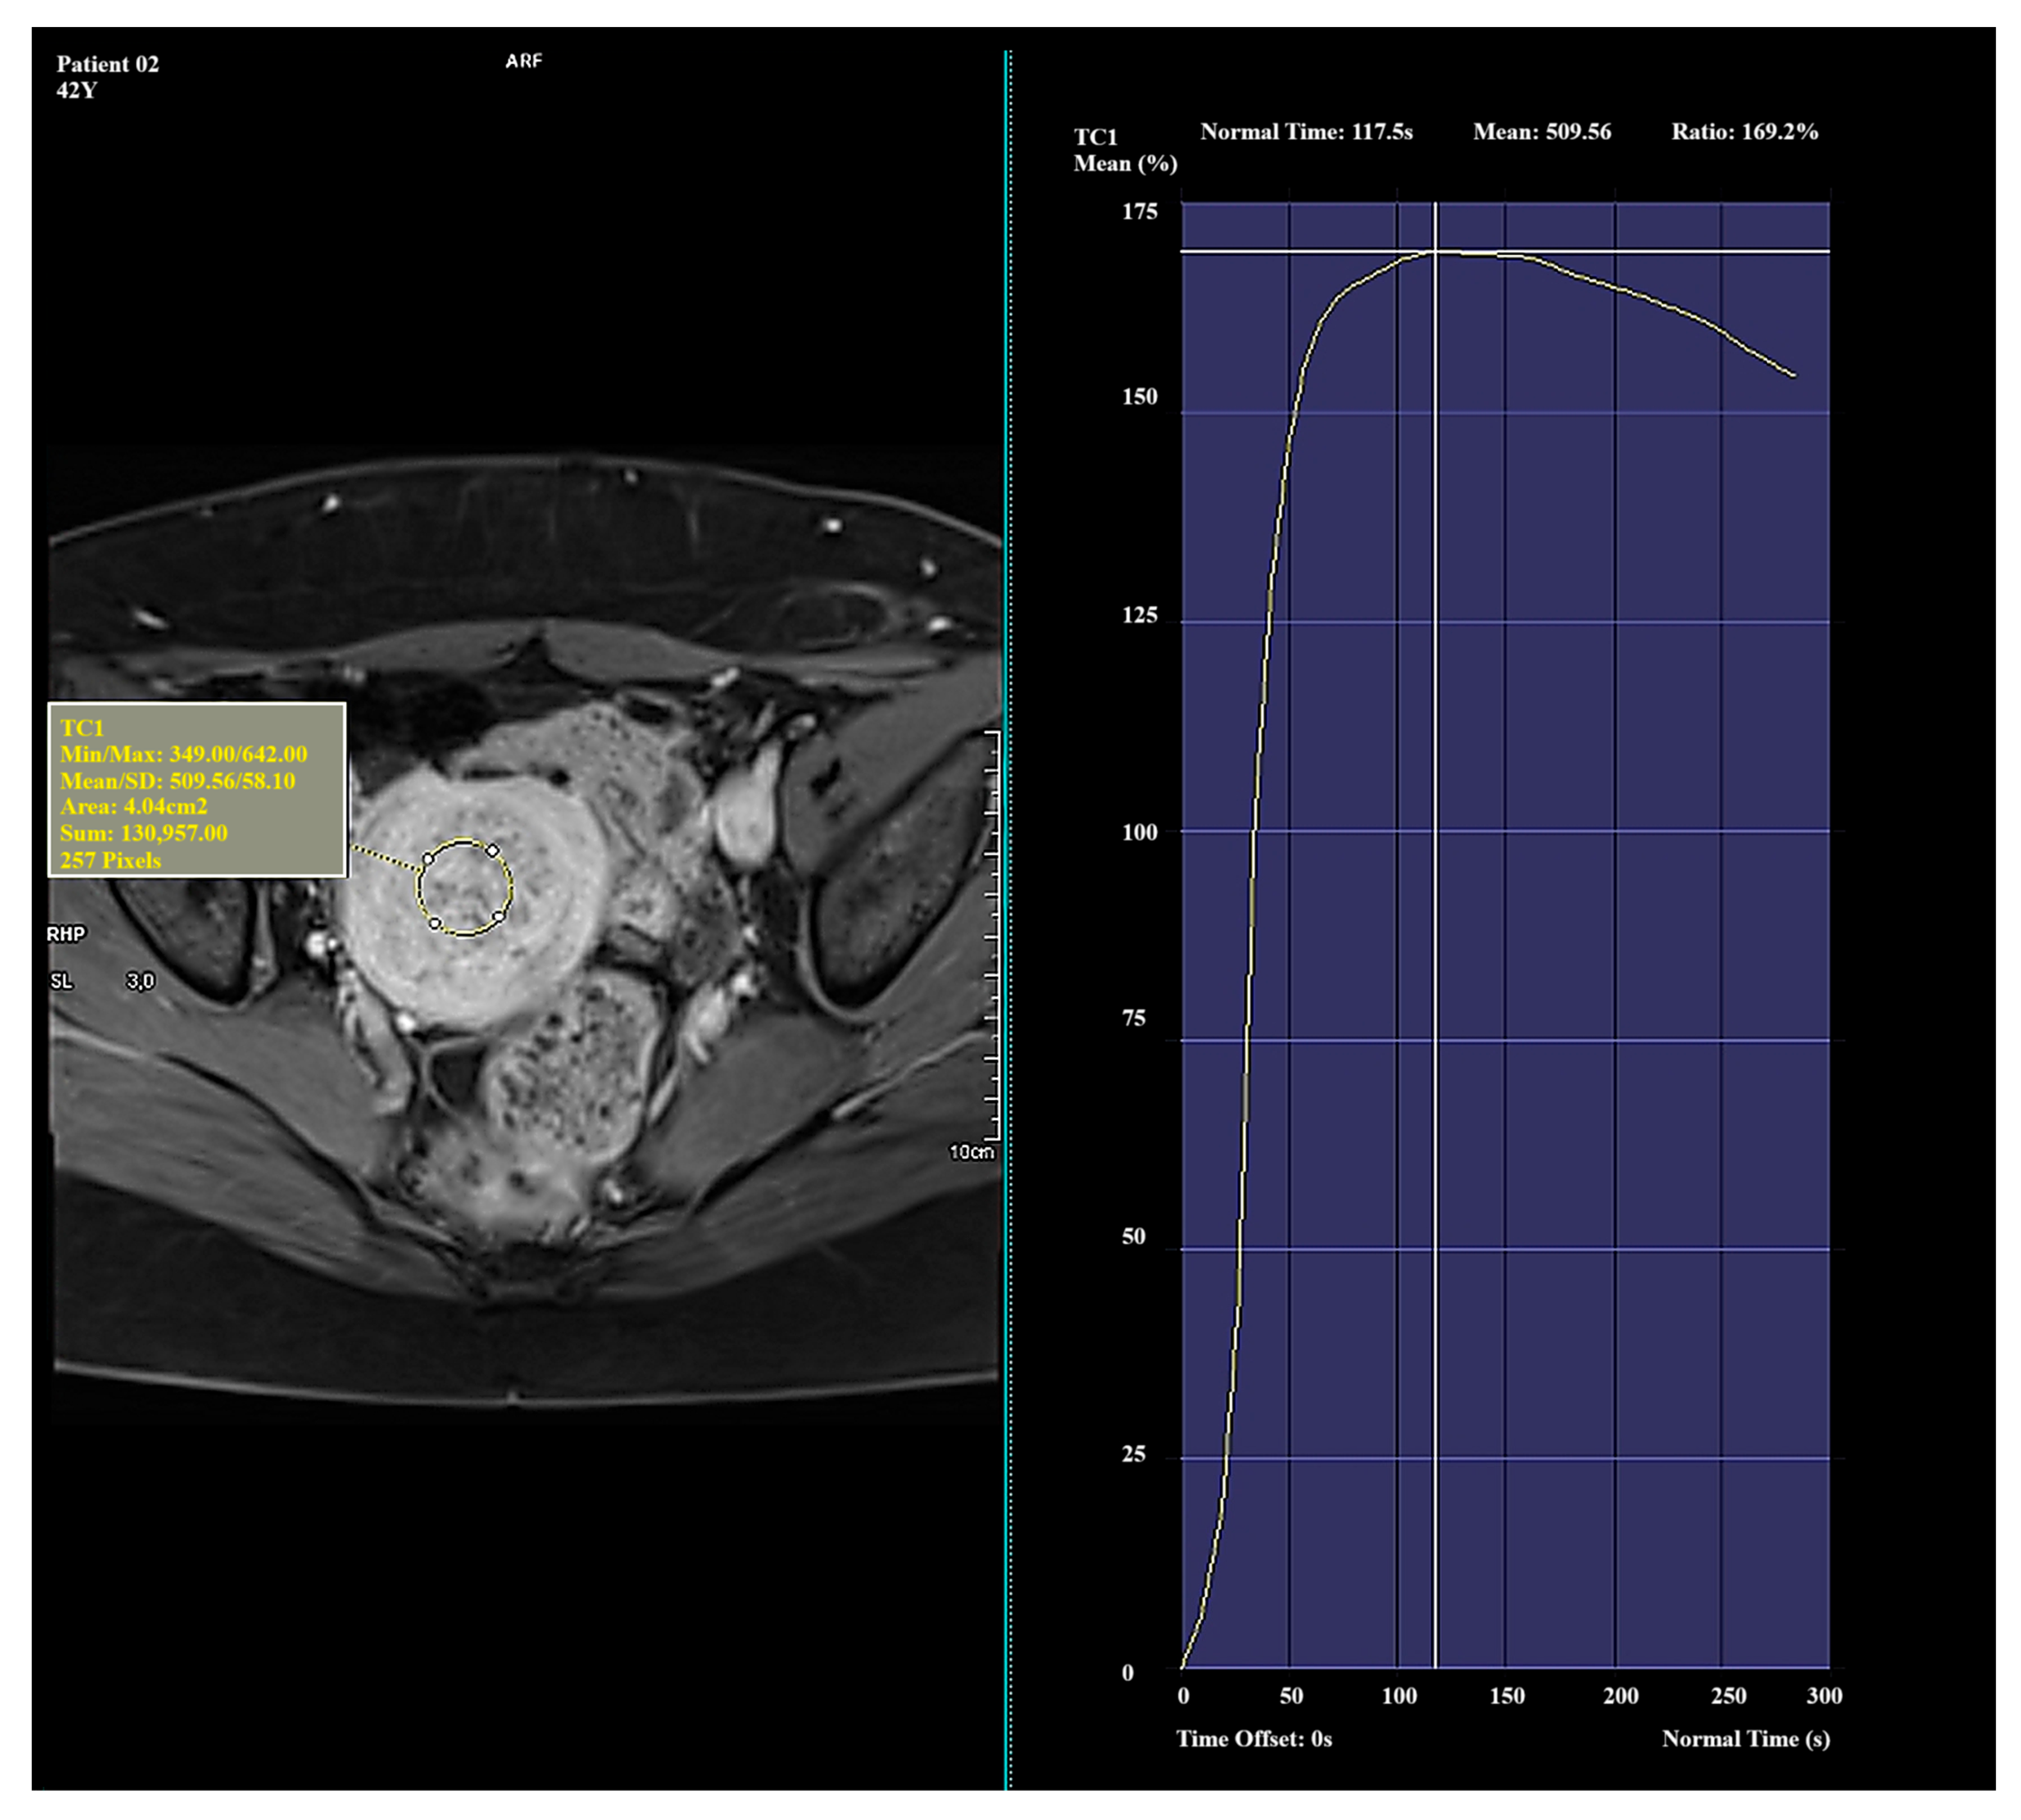

In Type I, the average Ratio was 156.96 ± 20.94 (Me = 156.89), the average TTP was 127.04 ± 42.05 (Me = 133.76), and the average Mean was 538.98 ± 55.51 (Me = 538.35). In Type II, the average Ratio was 122.04 ± 25.57 (Me = 113.85), the average TTP was 260.31 ± 33.91 (Me = 276.99), and the average Mean was 452.77 ± 8.38 (Me = 451.75). In Type III, the average Ratio was 37.60 ± 44.98 (Me = 33.41), the average TTP was 218.24 ± 89.10 (Me = 250.74), and the average Mean was 235.84 ± 111.76 (Me = 252.89). The mean values of perfusion parameters for each Funaki classification type are shown in Table 3.

In this study, a decrease in both Ratio and Mean values was observed from Type I to Type III, indicating a gradual decline in vascularization intensity. This trend reflects a progression from highly vascularized, biologically active myomas (Type I) to poorly vascularized lesions (Type III). The TTP value increased from Type I to Type II, which may suggest slower contrast enhancement dynamics in less vascularized myomas. In contrast, Type III exhibited a lower TTP value despite its low overall enhancement, possibly due to a limited dynamic enhancement range and the absence of a well-defined signal peak.

Significant and distinct differences in perfusion parameters were observed across the types. Type I lesions demonstrated strong and rapid enhancement and are likely the most biologically active. Type II lesions represented an intermediate category, showing clinical variability. Type III lesions—though rare in this study—displayed very low enhancement and signal intensity, which may correspond to fibrotic or ischemic changes. Due to the small number of Type III cases (n = 4), observations related to this group should be interpreted with caution and validated in a larger cohort. Representative enhancement curves for each Funaki classification type are illustrated in Figure 1, Figure 2 and Figure 3.

Figure 1. Example of amplification curve for Funaki Type I.